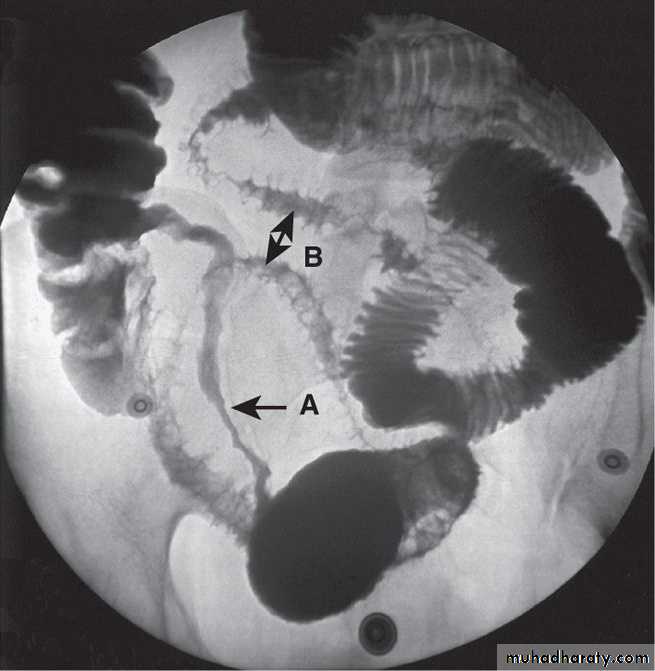

Barium follow-through showing terminal ileal Crohn's disease. A long stricture is present (arrow A), and more proximally there is ulceration with characteristic 'rose thorn' ulcers (arrow B).